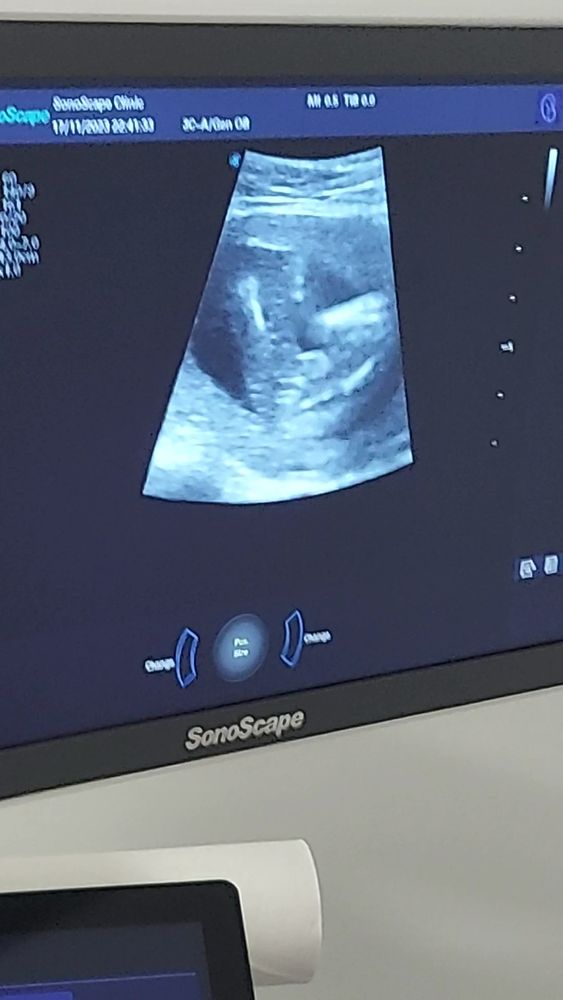

Сегодня узнаем кто в домике живет) (много фото узи) а вы как думаете?)

Плохое качество фото, видно что все они сняты между ног, но не чётко, вообще яичек нет вроде бы, значит девочка.

УЗИ 12 недель Точно девочка?)